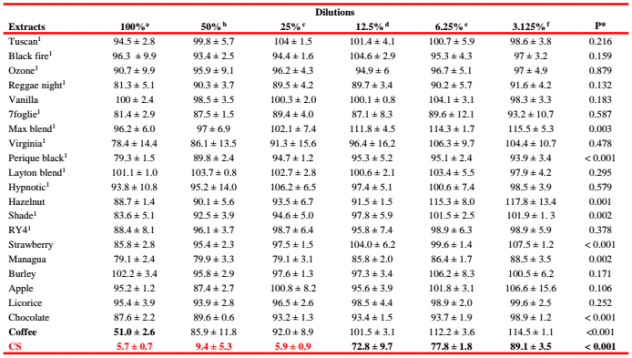

Интересные испытания были проведены в ходе токсикологических исследований, в которых изучали действие различных жидкостей на живые клетки. Интересно, что жидкости со вкусом кофе оказались наиболее неблагоприятной средой. Однако сравнивать с обычными сигаретами (CS) даже не стоит. В таблице ниже отображено количество выживших клеток.

Очень интересно и сравнение нескольких жидкостей электронных сигарет. При рассмотрении показателей рекомендуем обратить внимание на то, что самые худшие показатели у сигарет (CS) и жидкостей El Toro, сделанных на органических вытяжках из табачных листьев.